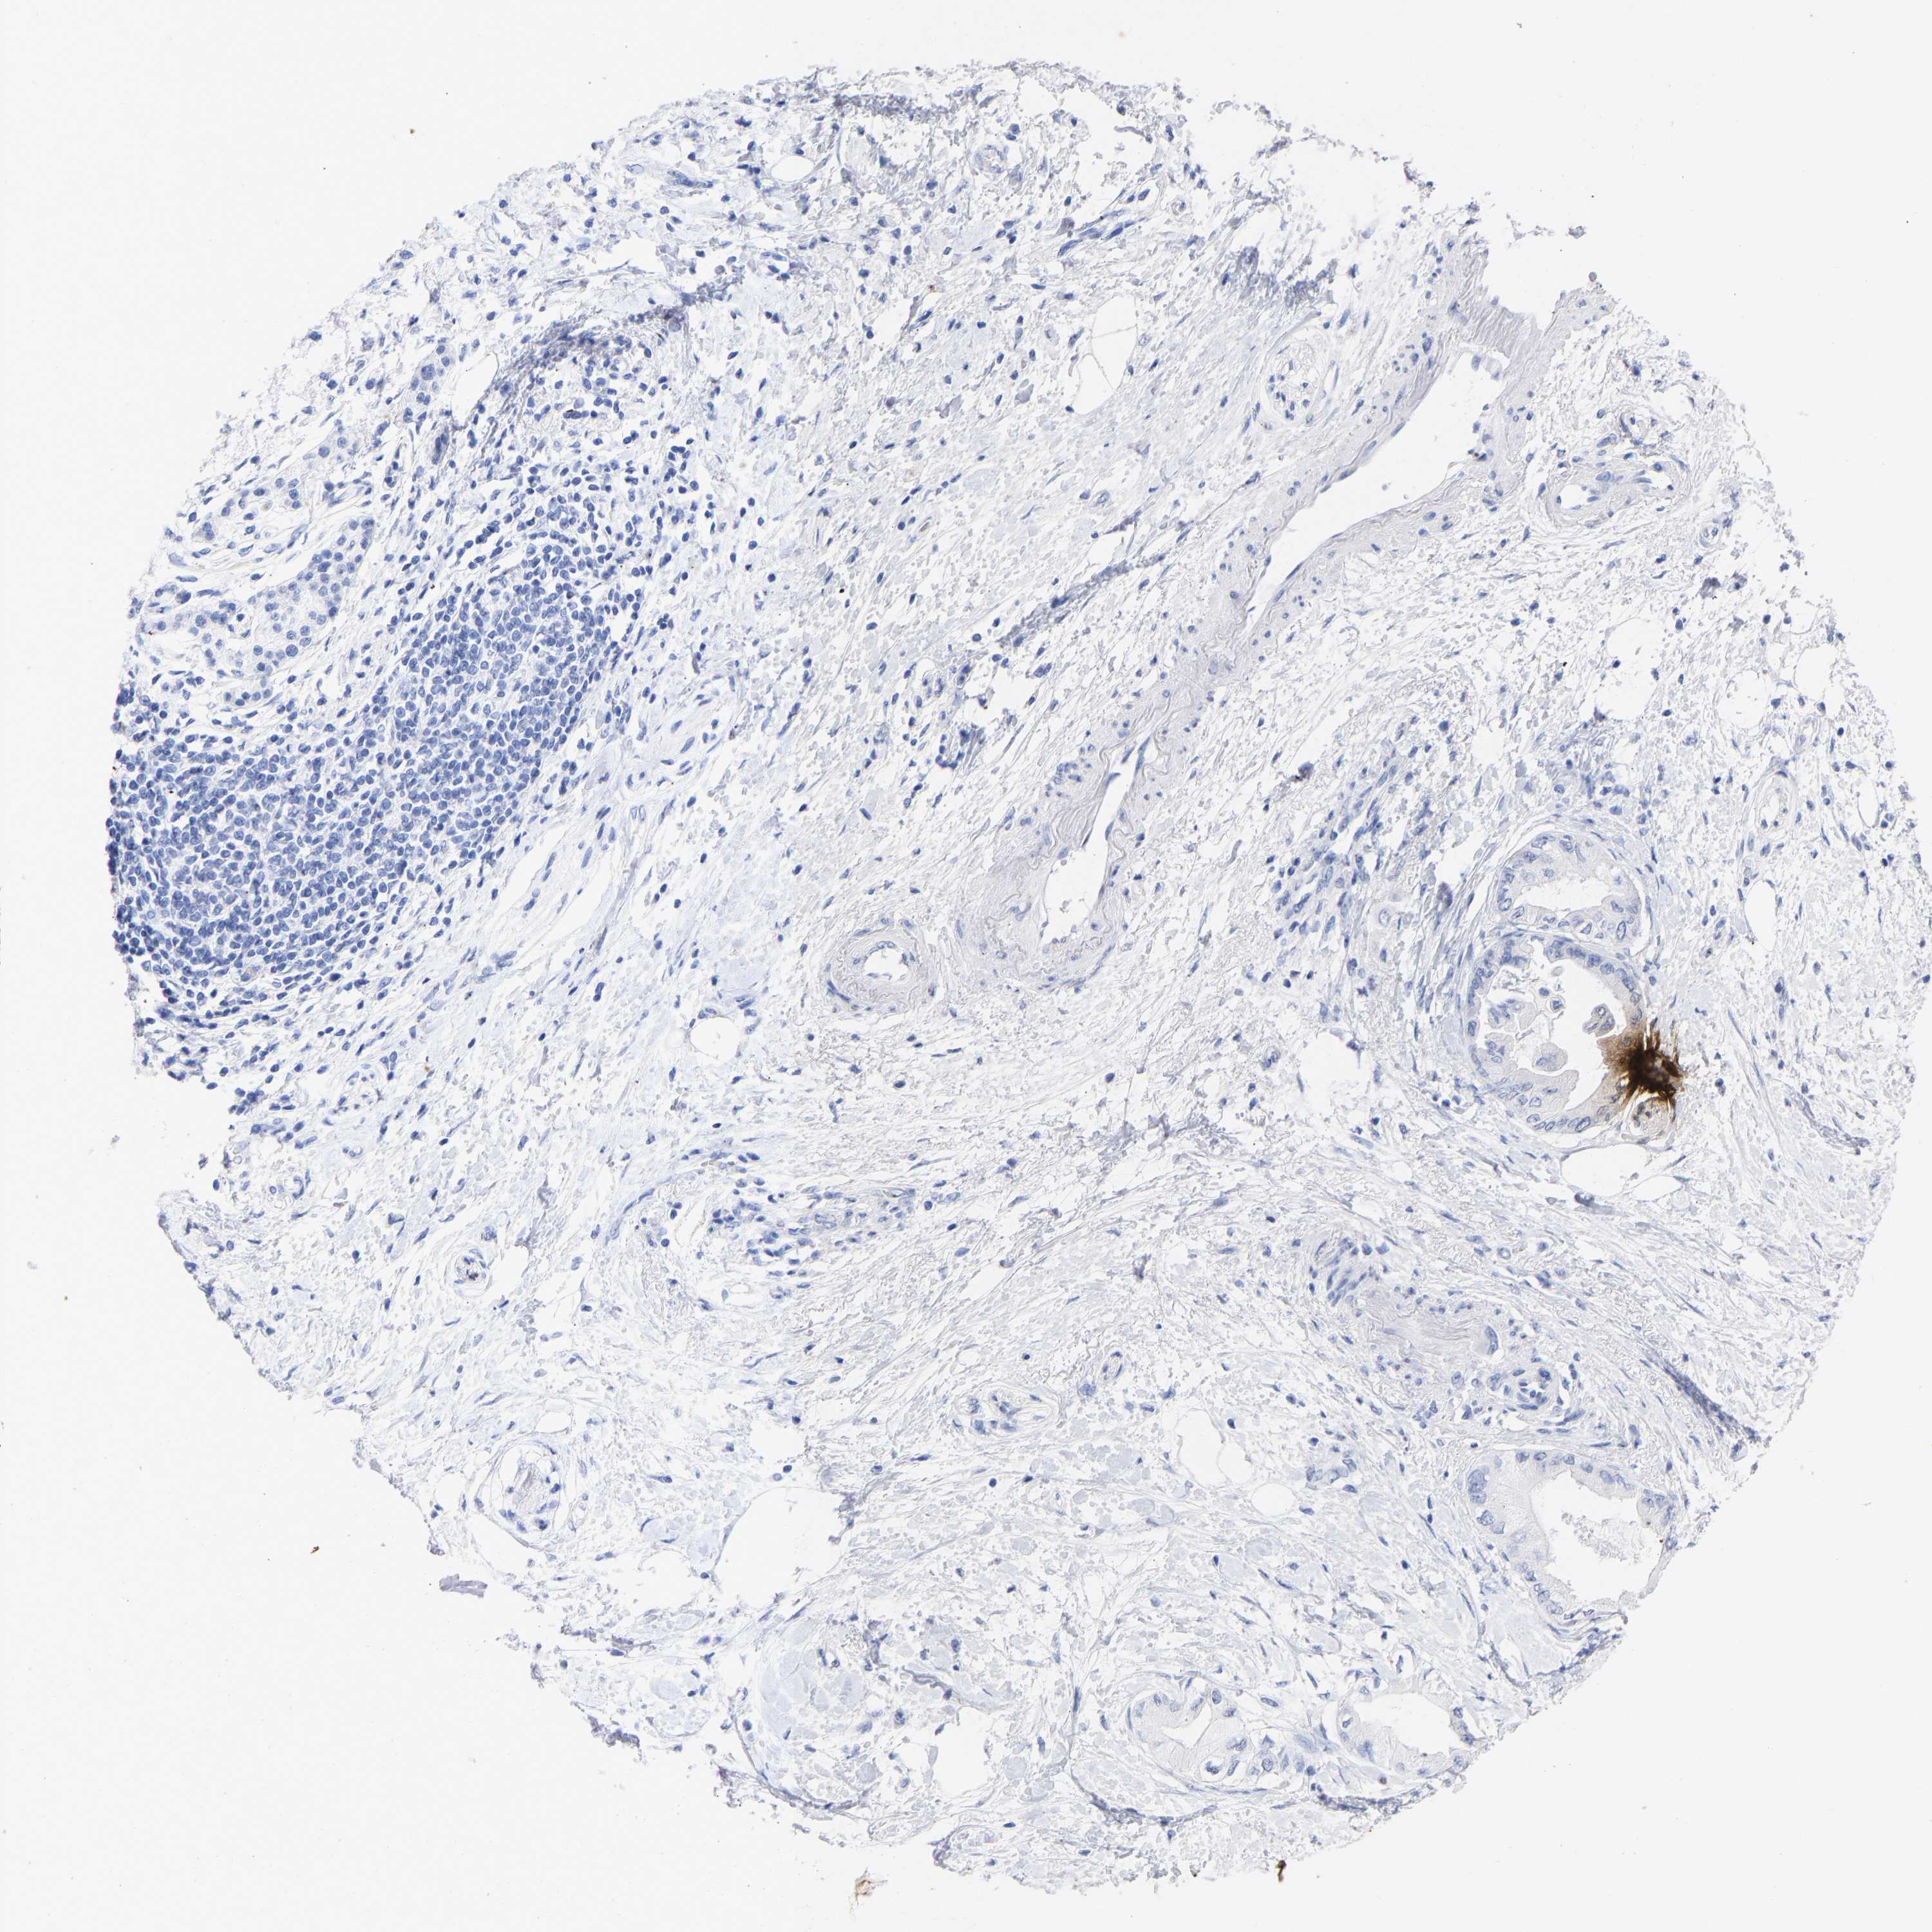

PANCREATIC CANCER - Protein expressioni

A mouse-over function shows sample information and annotation data. Click on an image to view it in a full screen mode. Samples can be filtered based on level of antibody staining by selecting one or several of the following categories: high, medium, low and not detected. The assay and annotation is described here.

Note that samples used for immunohistochemistry by the Human Protein Atlas do not correspond to samples in the TCGA dataset.

Antibody stainingi

Antibody staining in the annotated cell types in the current human tissue is reported as not detected, low, medium, or high, based on conventional immunohistochemistry profiling in selected tissues. This score is based on the combination of the staining intensity and fraction of stained cells.

Each image is clickable and will lead to virtual microscopy that enables deeper exploration of all samples and also displays staining intensity scores, fraction scores and subcellular localization as well as patient and tissue information for each sample.

Antibody HPA017917

Antibody HPA062908

Antibody CAB002153

Adenocarcinoma, NOS